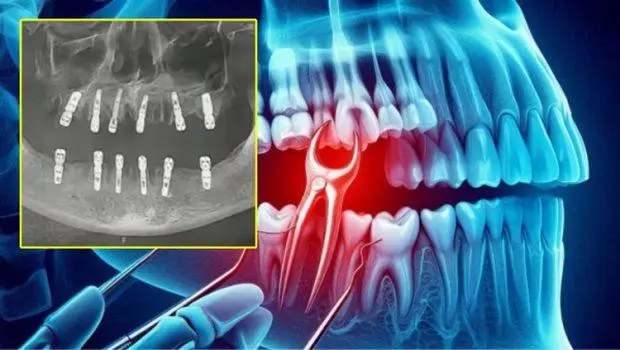

ಬೀಜಿಂಗ್: ಹಲ್ಲಿನ ಸಮಸ್ಯೆಗೆಂದು ಆಸ್ಪತ್ರೆಗೆ ಬಂದ ವ್ಯಕ್ತಿಯ 23 ಹಲ್ಲುಗಳನ್ನು ಒಂದೇ ದಿನ ಕಿತ್ತು ಹಾಕಿದ ಆಘಾತಕಾರಿ ಘಟನೆ ಚೀನಾದಲ್ಲಿ ನಡೆದಿದೆ ಅಷ್ಟುಮಾತ್ರವಲ್ಲದೆ 23 ಹಲ್ಲುಗಳ ಬದಲಿಗೆ ಹನ್ನೆರಡು ಹೊಸ ಹಲ್ಲುಗಳನ್ನು ಅದೇ ದಿನ ಇರಿಸಿದ್ದು ಇದೀಗ ರೋಗಿ ಹೃದಯಾಘಾತದಿಂದ ಮೃತಪಟ್ಟಿರುವುದಾಗಿ ವರದಿಯಾಗಿದೆ.

ಘಟನೆಯ ಕುರಿತು ಮೃತ ವ್ಯಕ್ತಿಯ ಮಗಳು ಸಾಮಾಜಿಕ ಜಾಲತಾಣದಲ್ಲಿ ಪೋಸ್ಟ್ ಹಾಕಿದ್ದಾಳೆ ಇದರಲ್ಲಿ ತನ್ನ ತಂದೆ ಧೀರ್ಘಕಾಲದಿಂದ ಹಲ್ಲುನೋವಿನ ಸಮಸ್ಯೆಯಿಂದ ಬಳಲುತ್ತಿದ್ದರು ಹಾಗಾಗಿ ಹಲ್ಲಿನಾಚಿಕಿತ್ಸೆಯಲ್ಲಿ ಪರಿಣತಿ ಹೊಂದಿದ ವೈದ್ಯರ ಬಳಿ ಚಿಕಿತ್ಸೆಗಾಗಿ ಕಳೆದ ತಿಂಗಳು ಆಗಸ್ಟ್ 14 ರಂದು ಯೋಂಗ್ಕಾಂಗ್ ನಲ್ಲಿರುವ ದಂತ ಚಿಕಿತ್ಸಾಲಯಕ್ಕೆ ಹೋಗಿದ್ದಾರೆ. ಈ ವೇಳೆ ಪರಿಶೀಲಿಸಿದ ವೈದ್ಯರು ಹಲ್ಲುಗಳನ್ನು ತೆಗೆಯಬೇಕಾಗುತ್ತದೆ ಅದರ ಬದಲಿಗೆ ಹೊಸ ಹಲ್ಲುಗಳನ್ನು ಇಡಬೇಕಾಗುತ್ತದೆ ಎಂದು ಹೇಳಿದ್ದಾರೆ ಎಂಬುದಾಗಿ ಪೋಸ್ಟ್ ಮಾಡಿದ್ದಾಳೆ.